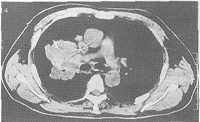

1.2 方法 CT导向仪为岛津SCT—4800TE全身CT扫描,带超薄层1mm及HRCT扫描。定位器为自制栅网格定位器(用废导管制成,每2根间距1cm)。选用特制穿刺套针进行穿刺。在病变相应皮肤表面放置栅网格定位器,选择有肿瘤中心层的CT扫描层为进针层面,并利用CT机上的激光十字定位灯标出进针点,测出进针深度及角度。常规消毒局部皮肤、铺巾、局麻。穿刺时嘱患者平静呼吸,进针达相应深度后再作CT扫描,反复调整进针方向,以明确针尖已在肺肿瘤中心。取出针芯,送入内径为0.1cm、长度为50cm的特制导管至肿瘤中心部位,然后缓慢退出套针。将导管留于肿瘤组织中,另一端固定于皮肤上,注入少量泛影葡胺后再次CT扫描,以确定导管在肿瘤组织中(图1)。10min后作胸部 X线透视,确定无气胸后将患者送回病房,进行局部微泵持续化疗。

图1 肿瘤置管术后注入泛影葡胺

Fig 1 Inject meglucamine diatrizoate after implanting tube in lung cancer